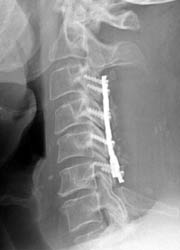

50-year-old male who presented with worsening gait, neck pain, upper

extremity pain, numbness, and occasional bowel and bladder incontinence. The

patient complained of increasing difficulty walking, neck stiffness, and leg

cramps, increasing upper extremity numbness, and dysthesia in hands and

forearms. The patient underwent C3-6 laminectomies with postero-lateral fusions.

AP and lateral radiographs taken 5 days after surgery demonstrate

typical laminectomy defects at C3-6. The posterolateral fusions appear intact

with bone grafting material faintly appreciated. The screws and plates are

intact and in appropriate positioning. |